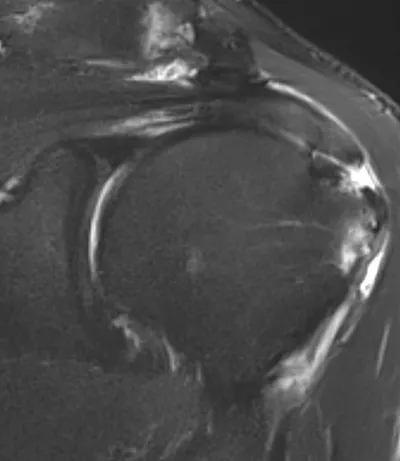

This collection contains 1 radiology images related to rotator cuff tear, including various imaging modalities such as X-rays, MRIs, CT scans, and ultrasound images commonly used in medical diagnosis and education.